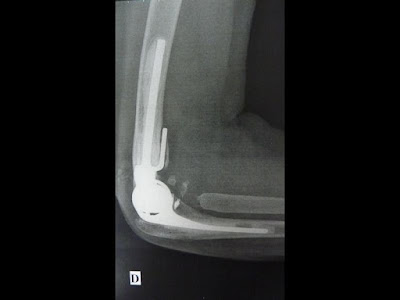

Arthroplastie :

remplacement prothétique au stade de séquelles